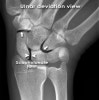

X-ray를 촬영합니다(PA view, lateral view, ulnar deviation and radial deviation view, flexion and extension view).

Scapholunate angle<30º, Radiolunate angle<15º를 보입니다.